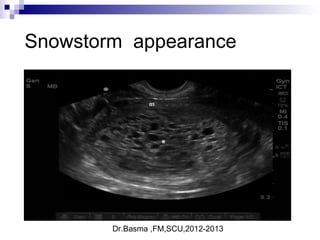

Hydatidform mole

Dr.Basma ,FM,SCU,2012-2013

Snowstorm appearance